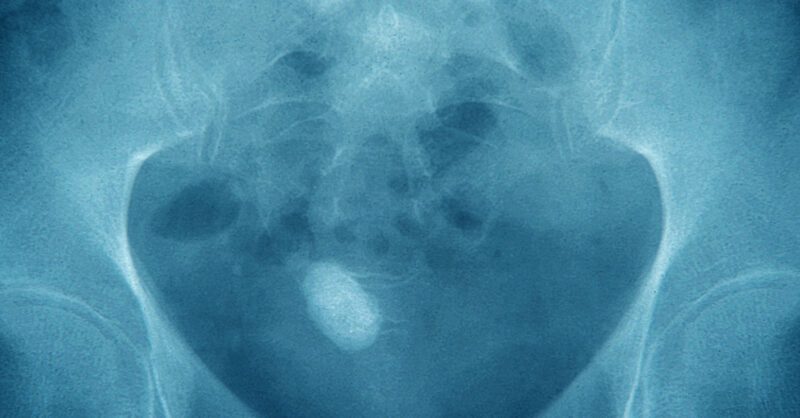

My kidney stone was the least painful part of the new year